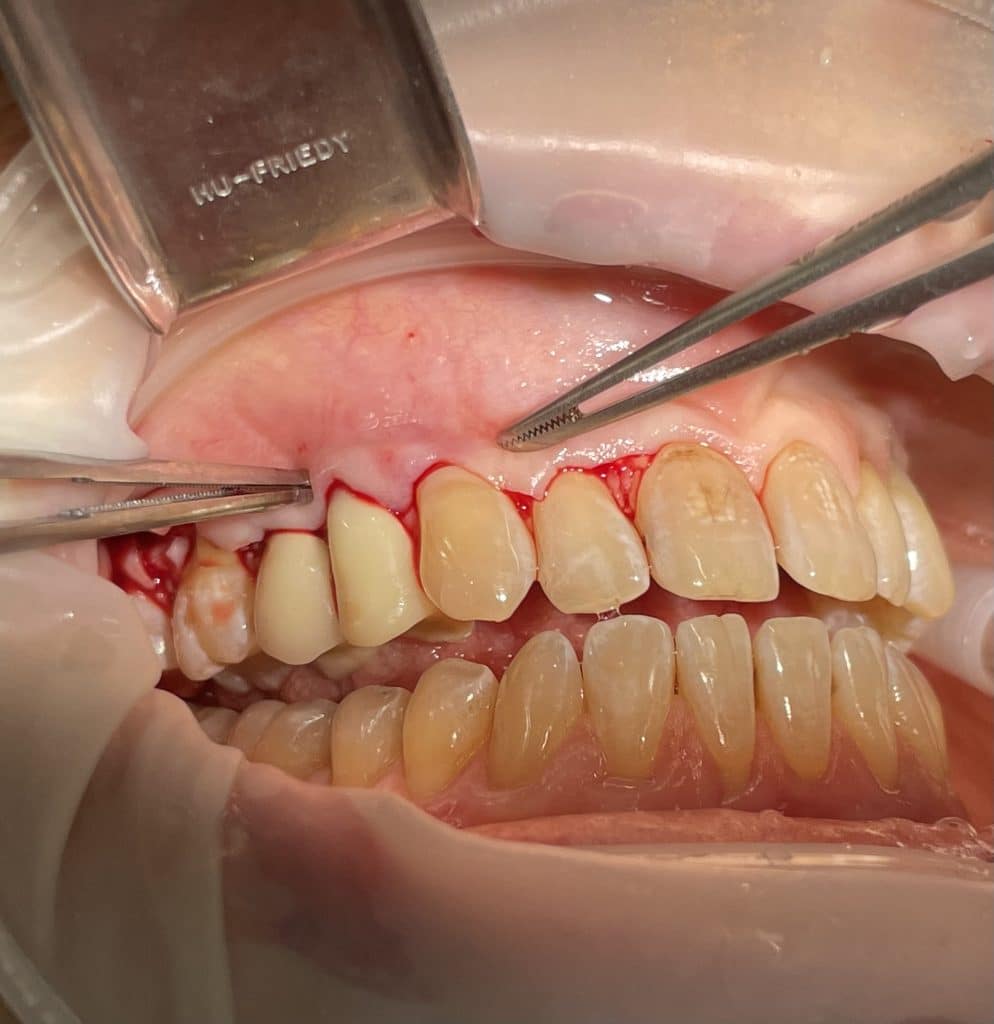

In quadrant 1, we initially removed caries and prepared tooth 14 for subsequent provisional cementation. We then performed a mucogingival surgery procedure, still utilizing the bilaminar technique with an envelope flap. The graft was harvested from the tuberosity area. The connective tissue was sutured to the periosteum, which had been left in place as the recipient bed. The primary flap was advanced coronally, covering the graft, and sutured with sling sutures in the most coronal position. In this case as well, the sutures were removed after 10 days.

paramarginal incision